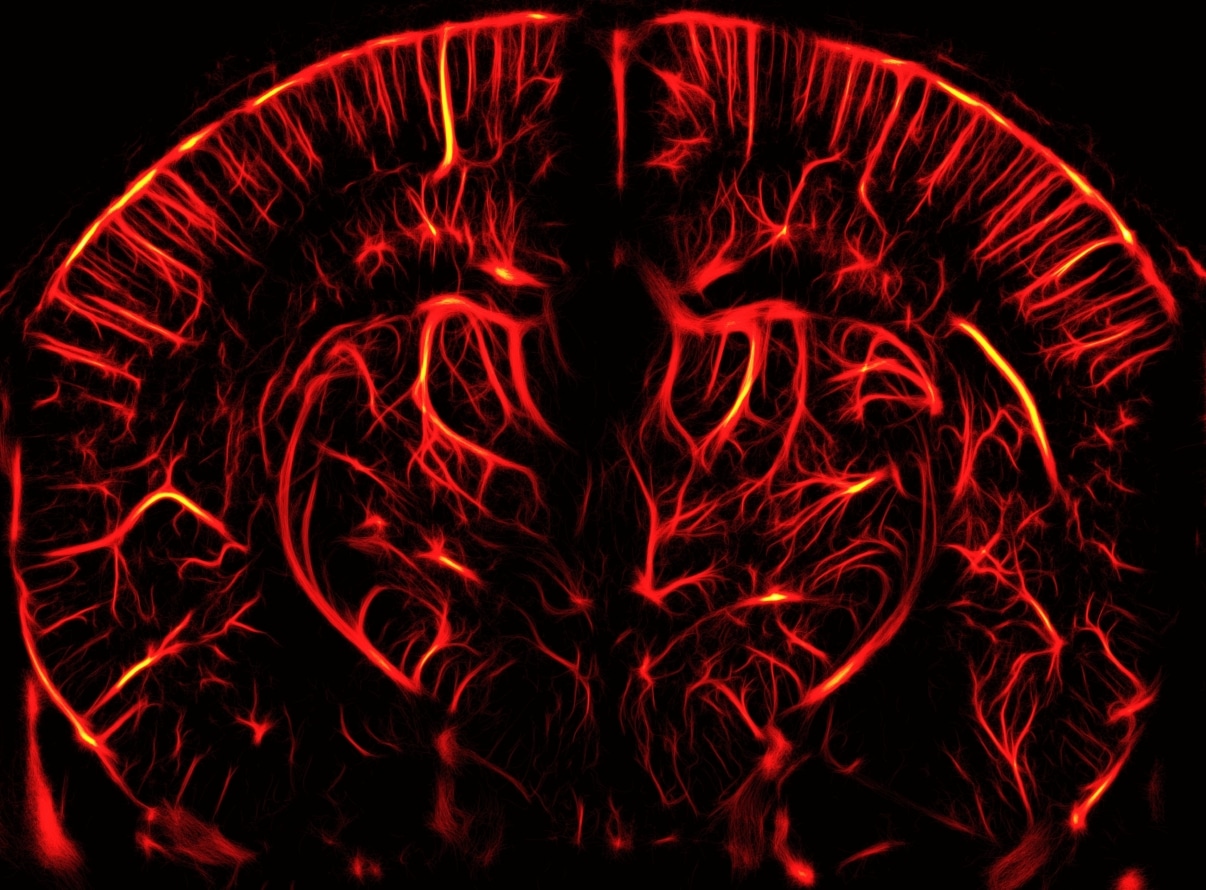

Ultrasound Localization Microscopy is a microbubble-enabled imaging technique that allows users of the Iconeus One functional ultrasound system to image blood vessels in the brain with amazing detail.

- High resolution: ULM can achieve an in-plane resolution of about 5 μm, allowing you to create high-resolution vascular maps of the brain.

- Microbubble tracking: With ULM, you can count and track individual microbubbles as they travel through the blood vessels, allowing even more detailed analysis.

- Blood velocity quantification: ULM enables the measurement of blood velocities in the mm/s range, including the direction of flow, enabling you to distinguish between different types of blood vessels (such as arterioles and venules).